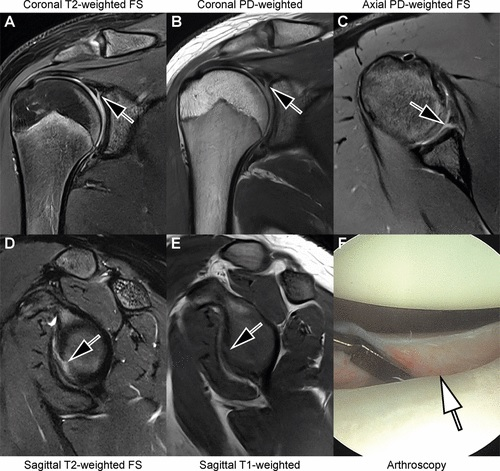

MRI is a good imaging modality for patients presenting with shoulder pain, due to its ability to visualize soft-tissue structures, Hahn and colleagues noted. Typically, patients undergo shoulder MRI exams that include high-resolution sequences in multiple planes using 2D fast spin-echo sequences. But these tend to translate into long scan times and can be skewed by motion artifacts, they wrote.

Accelerated sequences for shoulder MRI show promise but do produce noisier images. Hahn's group sought to explore whether adding deep-learning reconstruction could address this limitation.

The study included 105 patients who underwent 110 MRI exams. The investigators compared standard shoulder MRI sequences (9 minutes) and accelerated ones (3 minutes) for image quality and diagnostic performance; all patients had both. Standard sequences were reconstructed with conventional techniques, while the accelerated sequences were reconstructed with a conventional technique alone and with a conventional technique plus a deep learning algorithm (AIR Recon DL, GE Healthcare).

Two radiologists evaluated the MRI images for image quality and clarity using a four-point scale (with 1 representing poor and 4 indicating excellent). They also assessed images for artifacts using a four-point scale (with 1 meaning severe artifacts and 4 signifying no artifacts). Scores for each of three imaged planes were added for a total score of 3 to 12 for both image quality and artifacts.

The accelerated MRI shoulder exam sequences were accomplished in 67% less scan time, although they did have poorer image quality and artifacts compared with the standard sequences. But using the deep learning-based reconstruction helped, however.